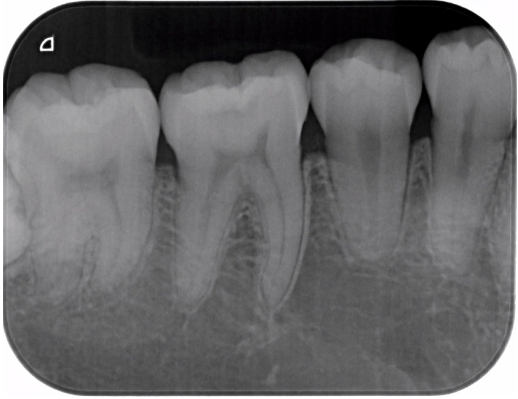

症例3

| 患者様データ | 20代 男性 |

| 来院時の主訴 | 「虫歯の治療をしたい。症状はない。」 |

| 術前検査結果 | 歯髄の生活反応有り、自覚症状無し |

| 医院の診断 | 無症候性可逆性歯髄炎 |

| ここがこだわりのポイント!☝ | 慢性う蝕の場合、術前症状がなくても、歯髄にまで細菌感染が生じているケースは珍しくありません。患者様は術前に症状の訴えはありませんでしたが、歯の神経にまで細菌感染が生じており、神経の除去を勧めたところ、歯髄保存療法を希望されました。MI治療が可能と判断したので、年齢も若いことから治療後は歯を極力削らない治療で終了しています。 |